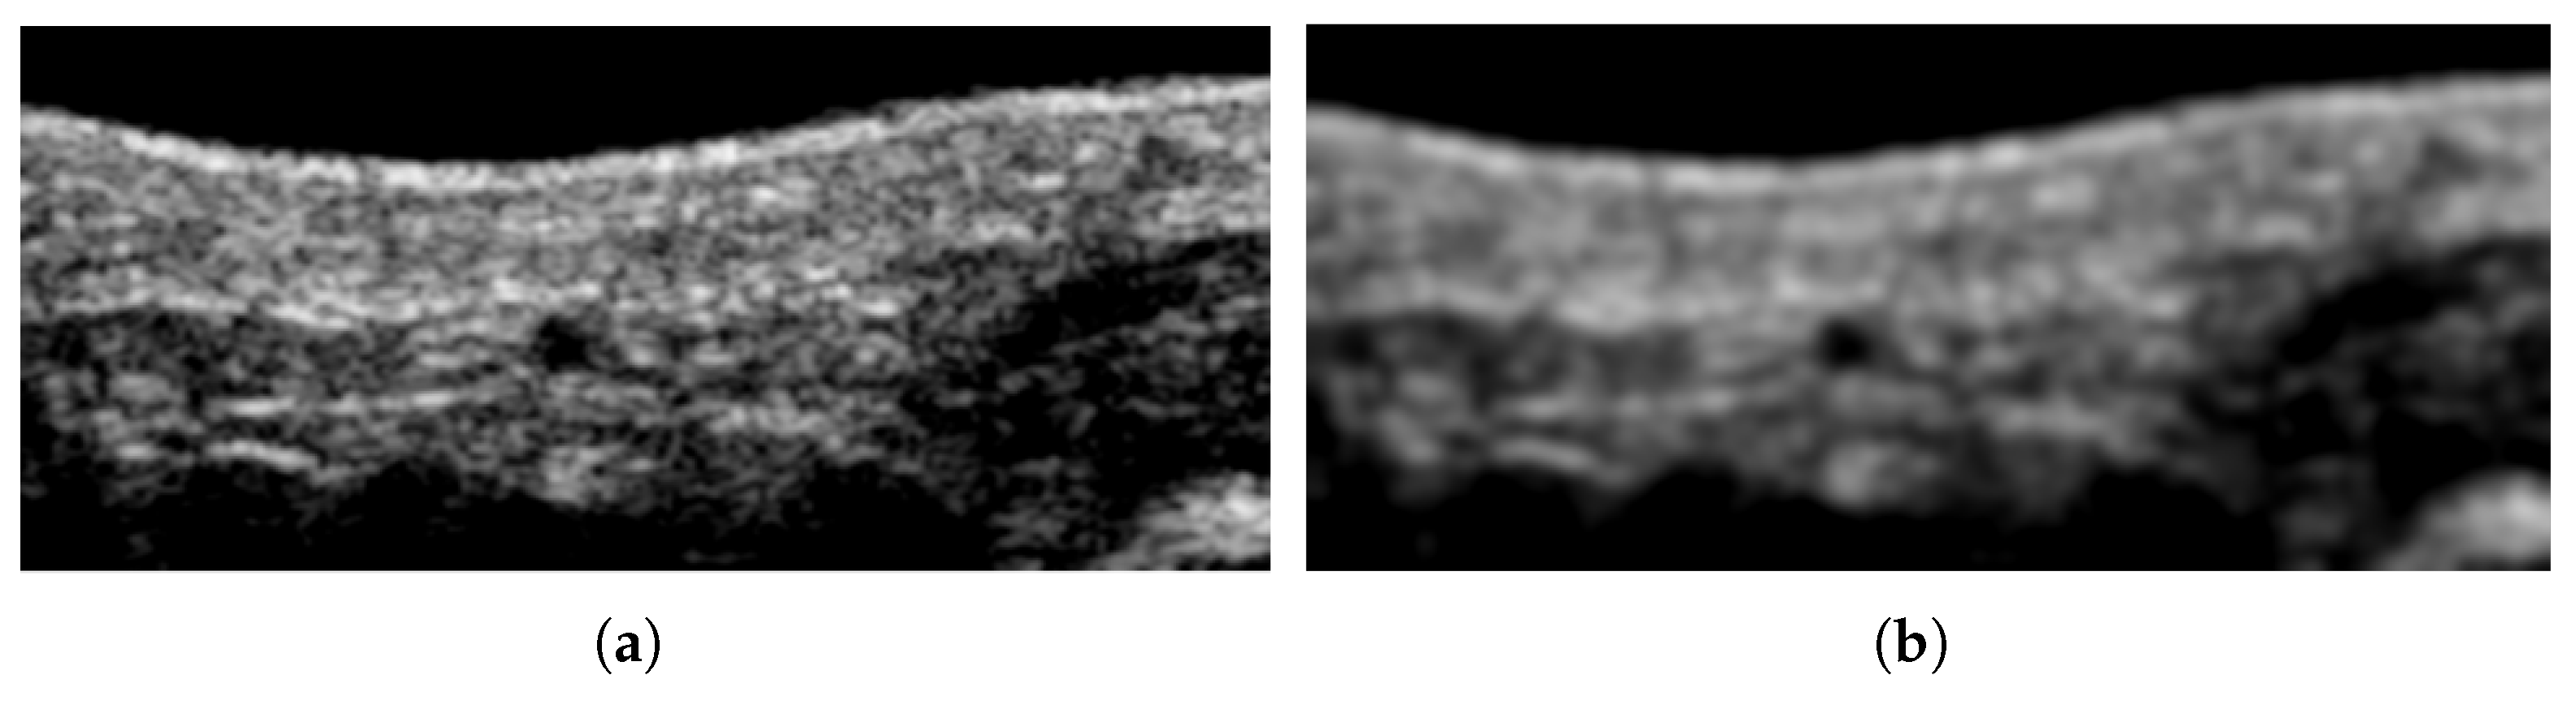

- Yu, Y.; Acton, S. Speckle reducing anisotropic diffusion. IEEE Trans. Image Process. 2002, 11, 1260–1270. [Google Scholar]

- Narayan, N.S.; Marziliano, P.; Kanagalingam, J.; Hobbs, C.G. Speckle in ultrasound images: Friend or FOE? In Proceedings of the 2014 IEEE International Conference on Image Processing (ICIP), Paris, France, 27–30 October 2014. [Google Scholar]